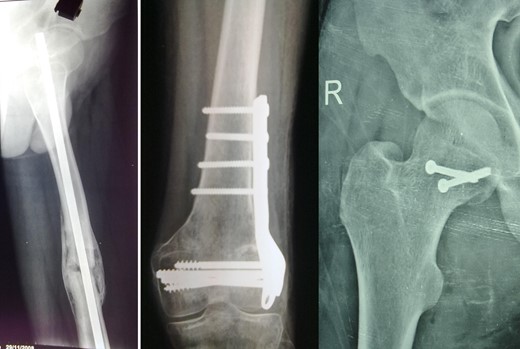

Blood parameters were within normal limits. X-ray of the pelvis revealed a right posterior hip dislocation with Pipkins's type II fracture (Rt) and ipsilateral distal medial condylar fracture with a fracture shaft of femur (Lt) (Figs 1 and 2). A CT scan confirmed the infrafoveal right-sided Pipkin's-II fracture of the femoral head (Fig. 3). A nerve conduction velocity study of lower limb suggested neuropraxia of sciatic nerve. Following attempt of closed reduction, CT scan and X-rays revealed incongruous reduction.

Initial X-ray: left thigh (anteroposterior view) and right knee (oblique view).

The right hip joint was approached via the Kocher-Langenbeck approach, fracture site was exposed with removal of fibrous tissue and the fracture involved mostly the infrafoveal non-weight bearing surface of the femoral head (Fig. 4). Following reduction of fracture, femoral head was fixed with two 4 mm cannulated cancellous screws that were introduced over a guide wire from the non-articular part under C-arm guidance (Fig. 5). Open reduction and plating was performed for the ipsilateral femoral condylar fracture. Closed reduction and intramedullary nailing of left femur was performed in the same sitting. The immediate postoperative X-ray was satisfactory (Fig. 6). The postoperative period was uneventful.